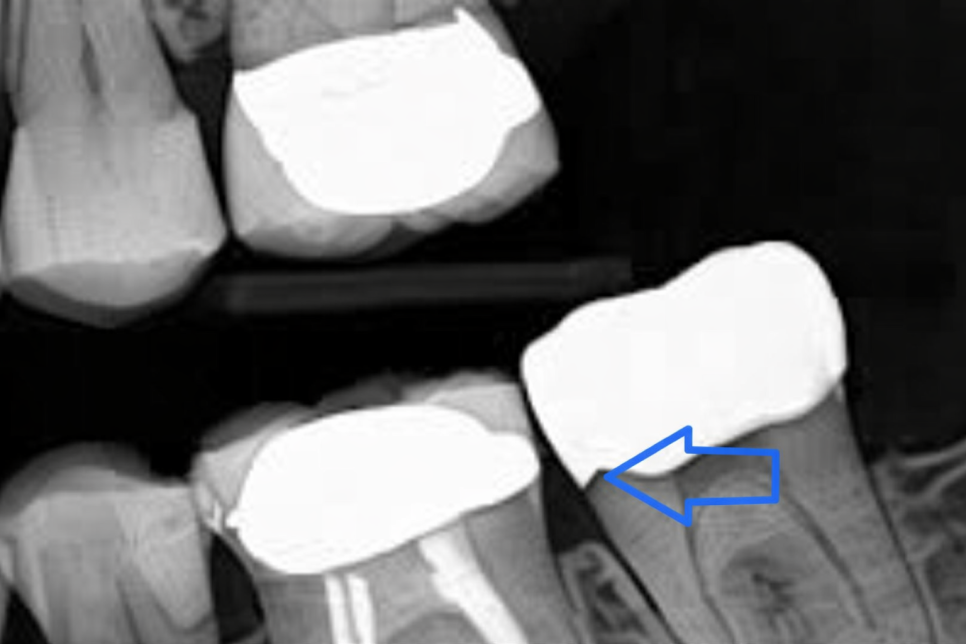

크라운이 씌워져 있는 치아가

지속적으로 아프고 시리다 호소하는 케이스.

단순히 치료 과정에서 가해진 충격에 의해

내부 구조가 예민해져 나타나는

증상이 아니라 보철 자체의 아주 작은

결함일 수도 있습니다.

사진처럼 크라운과 치아 사이 이행부가

긴밀하지 못하여(open margin)

치수가 충혈된 상태에 이르게 되었다면,

크라운과 어금니 사이를 잘 들여다봐

문제의 원인을 찾아 개선해 줘야 됩니다.

아주 작은 요소이기 때문에

진단 과정에서 미세 현미경을 사용하면

원인을 찾아내는데 큰 도움이 되죠.

또한 충치나 염증이 없는 상태이며

보철이나 다른 요소들도 정상인데

통증이 계속 지속되고 있다면,

매우 작은 균열이 생겼을

가능성도 있습니다.

기존에 씌워져 있던 보철과 치아 사이 이행부,

맨눈으로 관찰하기 어렵던 어금니 뒷쪽면(Distal) 등에

생긴 치아 파절을 확인하는 데 도움이 됩니다.